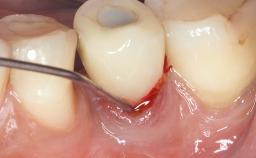

Surgical Management of Peri-Implantitis: Removal of Implant Due to Recurrent Infection Using an Implant-Retrieval Tool

A 65-year-old female patient was referred to the periodontist for assessment and management of infection associated with an implant at site 12. The general dentist had noted suppuration on probing during examination.